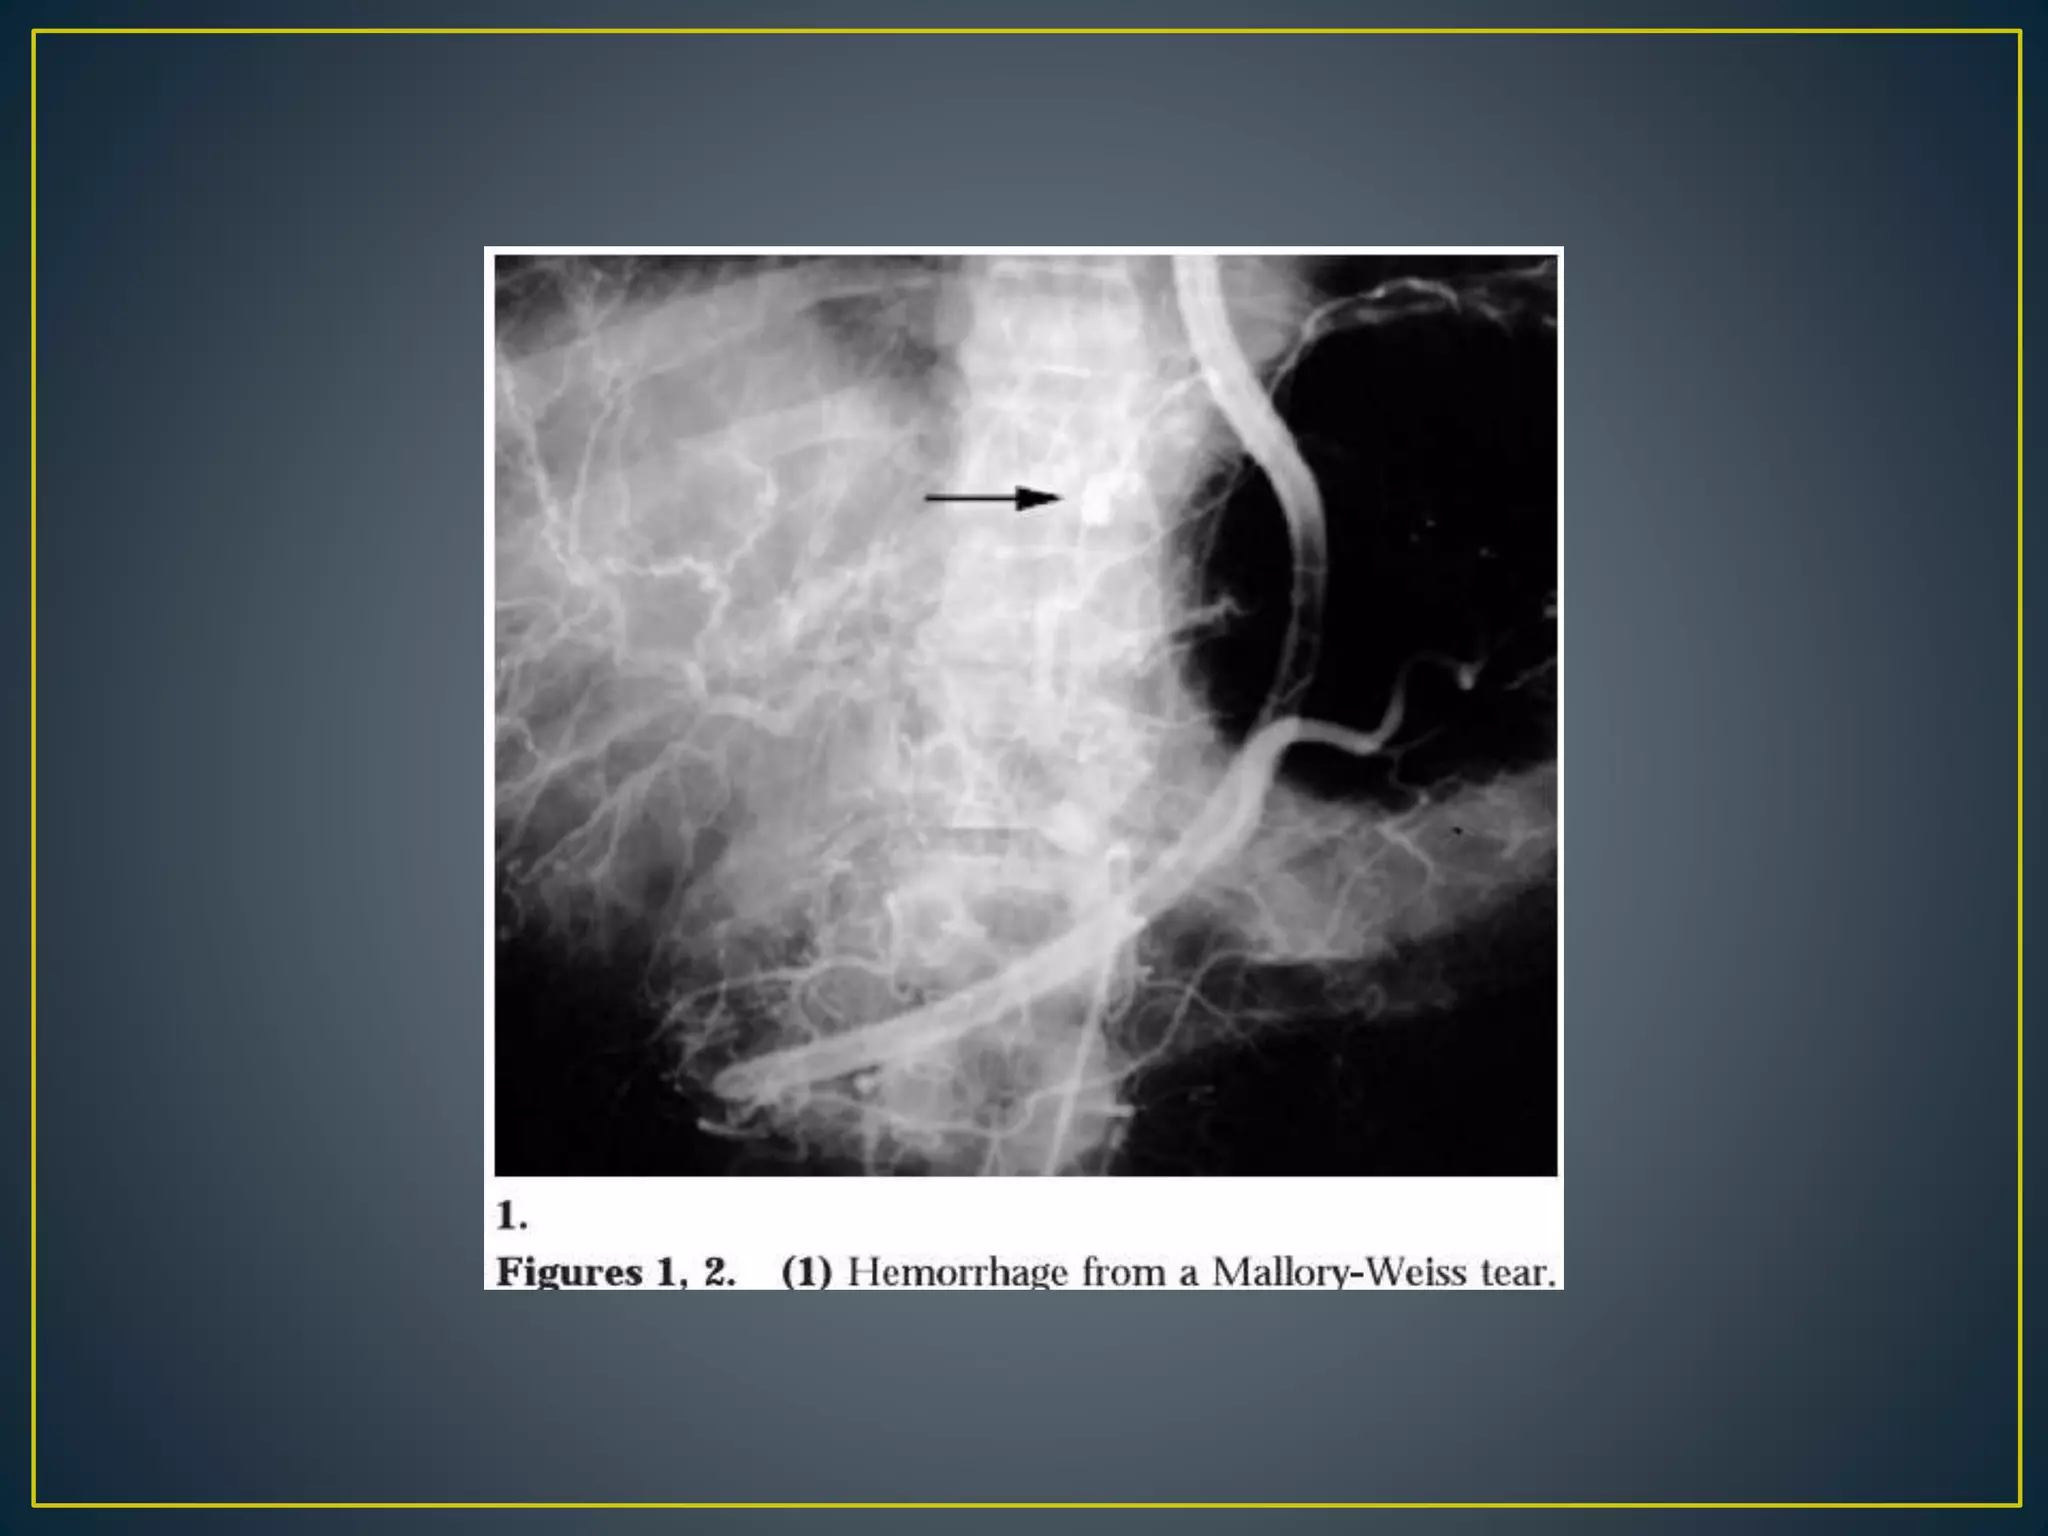

• The lesion is characterized by a tear in the proximal

gastric mucosa near the esophagogastric junction.

The clinical presentation is typified by an antecedent

history of vomiting, retching, or coughing followed

by hematemesis. The mean age for patients with this

condition is older than 60 years; 80% are men.

• Up to 90% of these lesions stop bleeding

spontaneously without specific intervention. Patients

with cirrhosis and portal hypertension with

coagulopathy are at greatest risk for morality, which

overall averages 3%.[